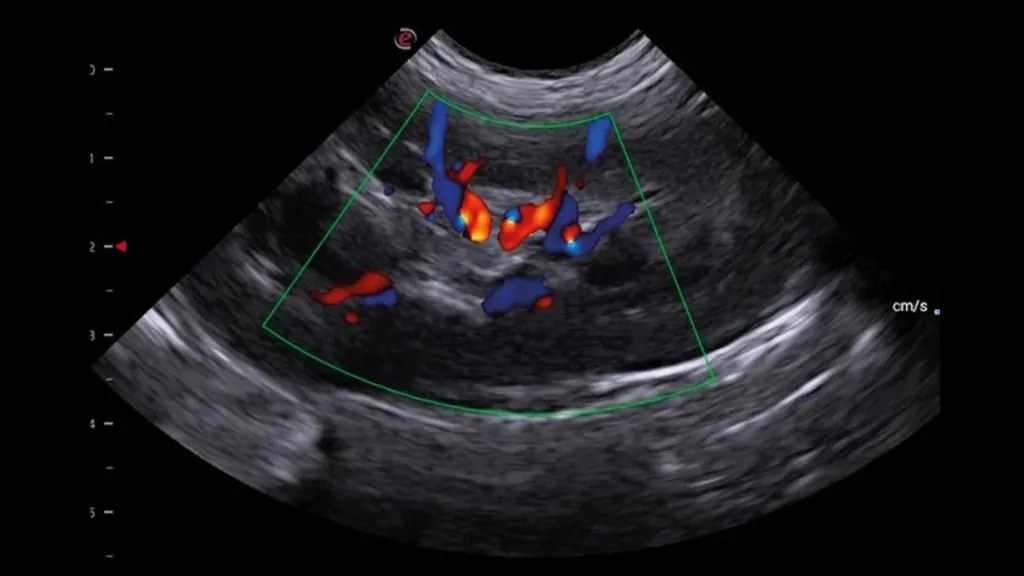

• Gerekli görülen durumlarda Doppler USG ile kan akımı analizi yapılabilir.

Karaciğer parankimi, portal/hepatik damarlar, safra kesesi ve biliyer sistem değerlendirilir.

Gerekli durumlarda Doppler ile vasküler yapıların analizi yapılabilir; portosistemik şant şüphesinde yönlendirici olabilir.